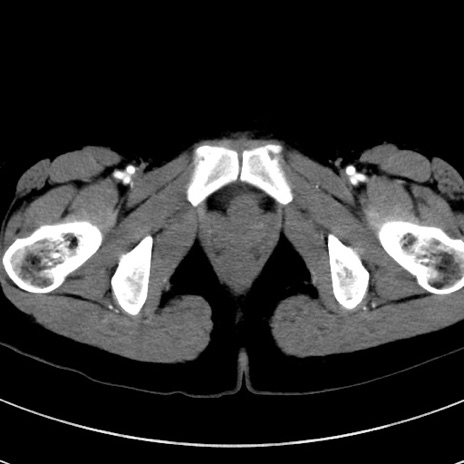

冠状断像

【症例】20歳代女性

【主訴】嘔吐、下腹部痛

【現病歴】昨日夕食後に嘔吐し下腹部痛が出現。本日になっても嘔吐持続し改善しないため来院。

【身体所見】意識清明、BT 37.2℃、BP 108/67mmHg、腹部:平坦、やや硬、下腹部正中から右にかけて圧痛あり、反跳痛軽度あり、tapping pain(+)。

【データ】WBC 13600、CRP 14.94